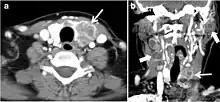

Fig. 9. A 58-year-old male patient with persistence PTC at thyroid bed with hypervascular nodal metastasis. a–c Transverse greyscale and colour Doppler neck ultrasound demonstrate hypoehoic soft tissue in the left thyroid bed (white arrow in a). There are a heterogeneous enlarged lymph nodes at level 2 and 3 with markedly increased vascularity (white arrow in b and c). d–f Enhanced axial CT images of the neck demonstrate a 2.7 × 1.4 cm hypodense soft tissue lesion anterior to the left carotid sheath (white arrow). There are left-sided enhancing abnormal and enlarged lymph nodes at cervical level 2 and 3 (black arrows).[1] Fig. 9. A 58-year-old male patient with persistence PTC at thyroid bed with hypervascular nodal metastasis. a–c Transverse greyscale and colour Doppler neck ultrasound demonstrate hypoehoic soft tissue in the left thyroid bed (white arrow in a). There are a heterogeneous enlarged lymph nodes at level 2 and 3 with markedly increased vascularity (white arrow in b and c). d–f Enhanced axial CT images of the neck demonstrate a 2.7 × 1.4 cm hypodense soft tissue lesion anterior to the left carotid sheath (white arrow). There are left-sided enhancing abnormal and enlarged lymph nodes at cervical level 2 and 3 (black arrows).[1]